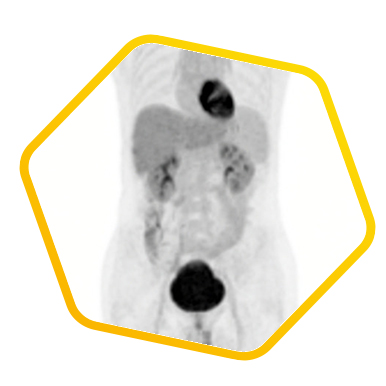

Liver Cancer

Multiple tracers are used to differentiate biochemical properties of liver lesion – Cancer Associated Fibroblast (Ga-68 FAPI uptake)

[C-11] Acetate and [F-18] FDG for hepatocellular carcinoma cellular differentiation (well and poorly differentiated)